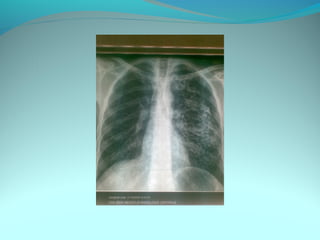

image radiologique bilaterale a type d’opacité en nappe occupant les

2/3 inf des du poumon pridominante a droite

Par ailleurs on note une opacité dense et homogene comblant les cds

costodiaph droit correspondant a une pleurale

DIAGNOSTIC :

Bronchopneumonie bilaterale